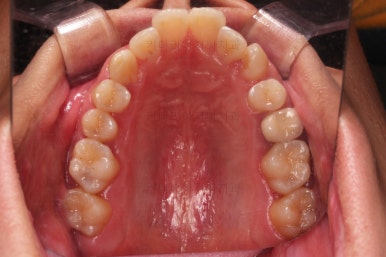

초진 시 입안의 모습입니다.

옆쪽에서 보면 치아와 치아가 1:1로 부딪히는데(화살표 표시) 좋지 못한 교합입니다.

윗니와 아랫니가 앞뒤로 지그재그 서로서로 껴있어야 좋은 교합인데 전반적으로 윗니가 앞으로 밀려있는 양상의 교합이에요.

장기적으로 치아, 잇몸 건강에 좋지 못하답니다.